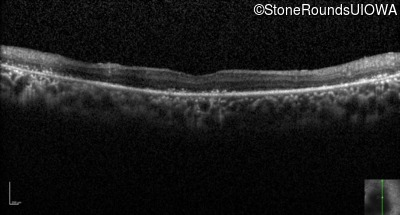

Optical Coherence Tomography - Right - Count Fingers

Exemplar / OCT Stack